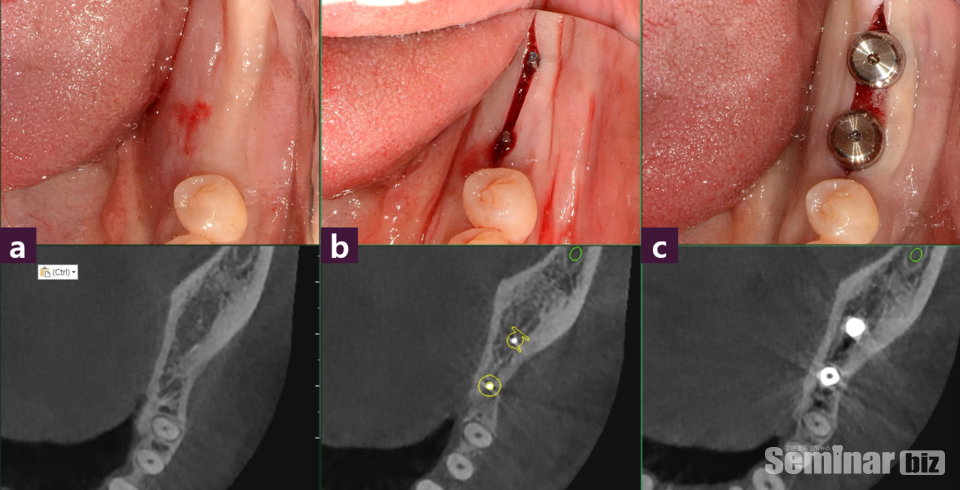

최소침습적 임플란트 치료를 지향하는AMII(Academy of Minimally Invasive Implantology,최소침습임플란트학회)에서는 최소한의 손상(절개, 골삭제, 이식재사용)과 최소한의 수술 횟수를 구현하기 위한 여러 치료술식을 개발하여 최소침습용 MagiCore 임플란트의 식립을 추천하는데 특히 간편하게 정교한 시술을 돕는 Magic GPS (GuidePinSystem)를 사용하면,

2.치조골내Magic Guide Pin을 삽입 후(internal marker) CT 촬영및 분석하고,

3.시술시 Magic Guide Pin을 드릴 내부에 끼운 채(internalguide) 로 식립구를 형성하는 치료가 가능하기 때문에 현재 사용되고 있는 통상적인 digital guide에 비해 매우 간편하고 정교한 진단과 시술을 유도하는 유용한 가이드 시스템이다 (그림1,2)

이 시스템은 일반적인 digital guide와 달리 CT 촬영의 error, 또는 환자의 움직임이나 떨림(tremor)의 영향을 최소로 받기 때문에 정확할 뿐 아니라 즉시 적용이 가능하며시술중에도 필요에 따라 수정이 용이하고 기존 surgical stent(external guide system)의 부피, 추가 비용, 드릴 시 조직열손상 가능성에 대한 술자와 환자의 부담 등을 획기적으로 줄임으로써 제 2대구치, 즉 최후방 치아를 포함한 모든dailyimplantpractice에 적용할 수 있다.